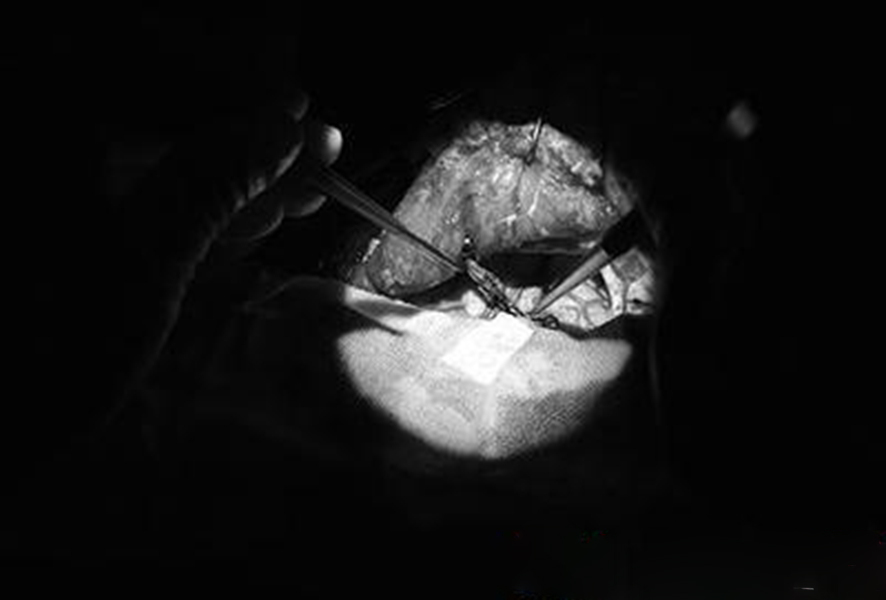

幼兒煙霧病腦手術

幼兒頭部手術煙霧病

煙霧病幼兒頭部